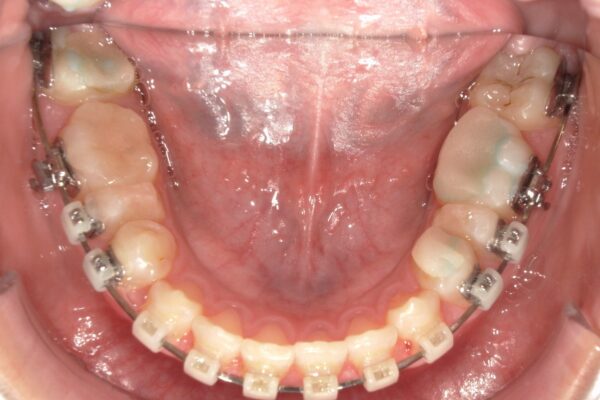

③装置装着1年1か月後:こだわりのタイミングでの抜歯

この段階で、事前に根管治療を終えていた下顎左右の5番を抜歯しました。 一般的な矯正では治療開始前に抜歯しますが、本症例では「先に噛み合わせの高さを改善することを優先した」ため、あえてこの時期に抜歯を行いました。

④装置装着1年6か月後:スペース閉鎖とエラスティック

「ループメカニクス」というワイヤーの形状を利用して、抜歯したスペースを閉じていきました。この際、患者さんに「エラスティック(矯正用ゴム)」を併用していただくことで、上下の奥歯を理想的な位置関係(Ⅱ級関係の改善)へと導きました。